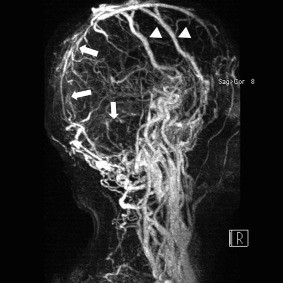

【摘要】:目的探讨MRV对不同时期脑静脉与静脉窦血栓形成(CVST)的诊断价值。方法分析15例CVST患者,同期行MRV和DSA检查,将3D CE-MRV及2D TOF-MRV与DSA进行

磁共振无对比剂血管成像技术(MRA、MRV)的临